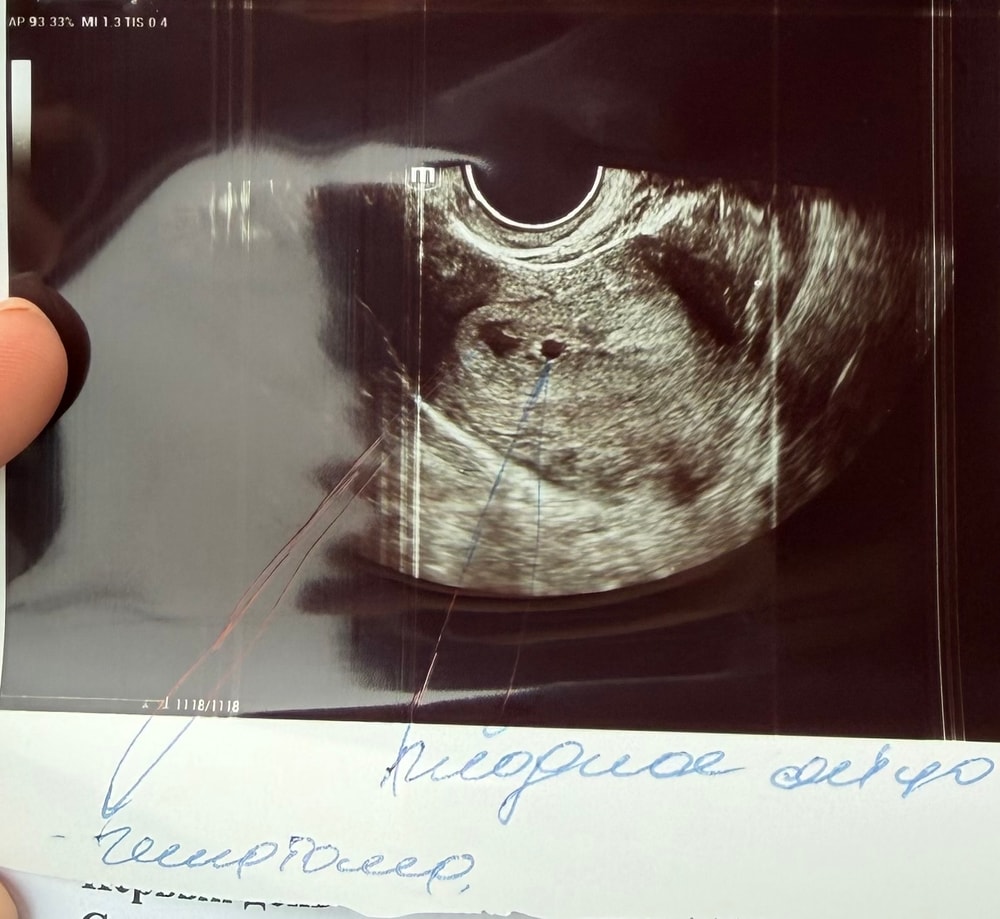

9,3 недели сегодня поставили не развивающуюся беременность 7-8 недель нет сердцебиения. Со вчерашнего дня тянет живот. В 7 недель была на узи было сердцебиение. Не ждать чуда и идти на вакум( не могу найти в нашем городе) медикаментозное выйдет все? Кто делал препаратами и на таком сроке?

6,4 недели сердцебиение видео по пульсации на узи но пока не прослушивается, пя 7мм